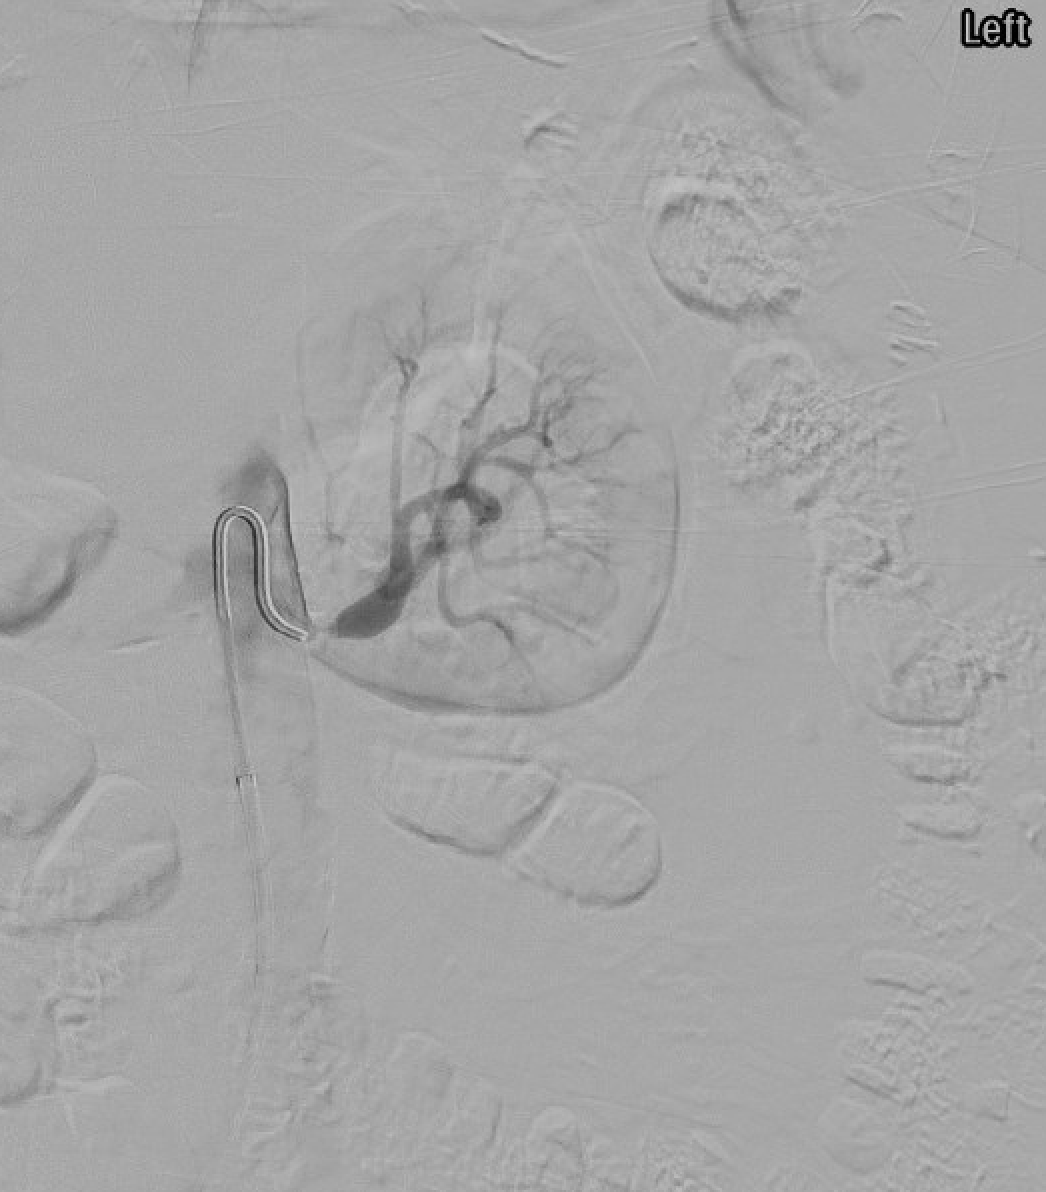

Selective angiogram demonstrating severe left renal artery stenosis — high-grade ostial narrowing consistent with atherosclerotic renal artery stenosis.

Mid to distal main renal artery and branches; "string of beads" on angiography in medial fibroplasia (most common subtype); young to middle-aged women

Kidney length: viable >8 cm; poor recovery if <7 cm or resistive index >0.80